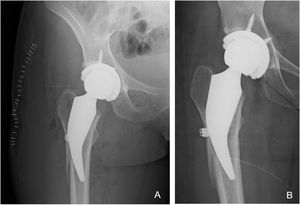

Complicaciones y revisiones: Intraoperatoriamente se detectaron cinco casos con fractura, cuatro de área proximal de calcar (incompletas) que fueron tratadas con cerclaje de alambre en el mismo acto quirúrgico primario (uno progreso a aflojamiento y debió ser revisado a los dos años de cirugía [1,1% de la serie]) y un caso con fractura de la cortical lateral en un paciente con coxa valga pronunciada que también fue tratado con cerclaje de alambre en el mismo acto quirúrgico del reemplazo primario. La consolidación de la fractura de cortical lateral fue antes de los tres meses, y no progreso a aflojamiento. Solo se limitó la carga con andador por los primeros 45 días (fig. 2). Todos los casos de fracturas intraoperatorias fueron dentro de los primeros 30 casos realizados con este implante. Postoperatoriamente se registraron un caso de luxación traumática que fue resuelta con reducción cerrada, una infección superficial de herida quirúrgica que resolvió con tratamiento clínico y antibioticoterapia (tabla 2).

La imagen muestra a una mujer de 32 años que se sometió a una ATC por osteonecrosis de la cadera derecha. A) Radiografía postoperatoria del mismo paciente con RTC con fractura de cortical la femoral lateral intraoperatoria tratada durante la cirugía con cerclaje de hilo trenzado de monofilamento. B) Radiografía AP que muestra un vástago bien fijado sin hundimiento y una cortical femoral lateral consolidada y una buena fijación a los seis meses de seguimiento.